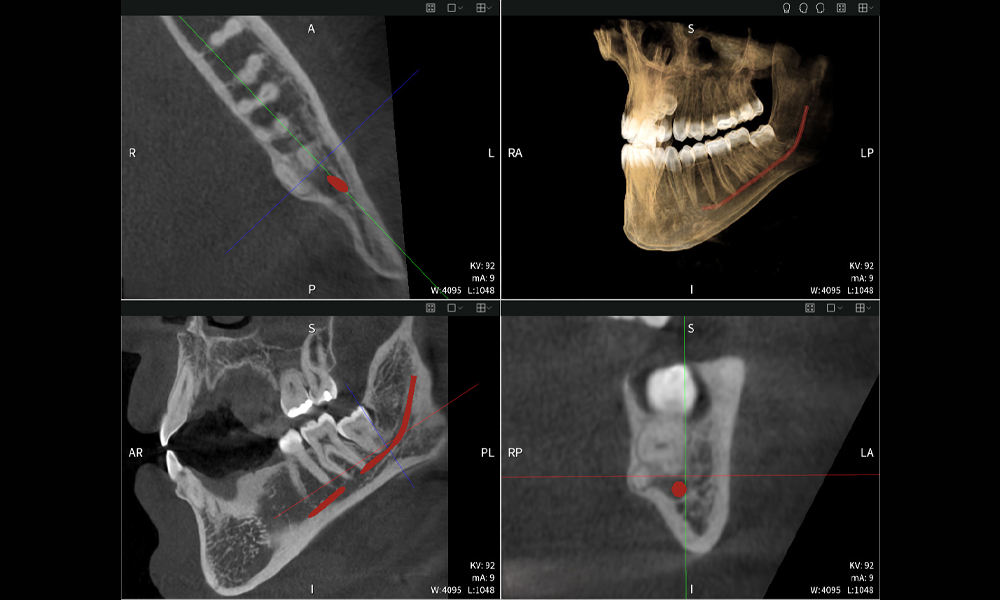

Abbildung a

- Oben links: Axiale Schnittansicht des linken Unterkiefers (Region 38) mit Darstellung des Nervus alveolaris inferior (rot) in unmittelbarer Nähe zu den Wurzeln des Zahns 38.

- Oben rechts: 3D-Rekonstruktion des gesamten Unterkiefers zur Orientierung. Der rot markierte Nervus alveolaris inferior verdeutlicht seine Lage im Kieferknochen.

- Unten links: Sagittale Ansicht des Unterkiefers (Region 38), die die enge räumliche Beziehung zwischen den Wurzeln und dem Nervenkanal verdeutlicht.

- Unten rechts: Koronale Ansicht des Unterkiefers (Region 38) entscheidend für die Beurteilung der räumlichen Lage der Wurzeln zum Nerven.